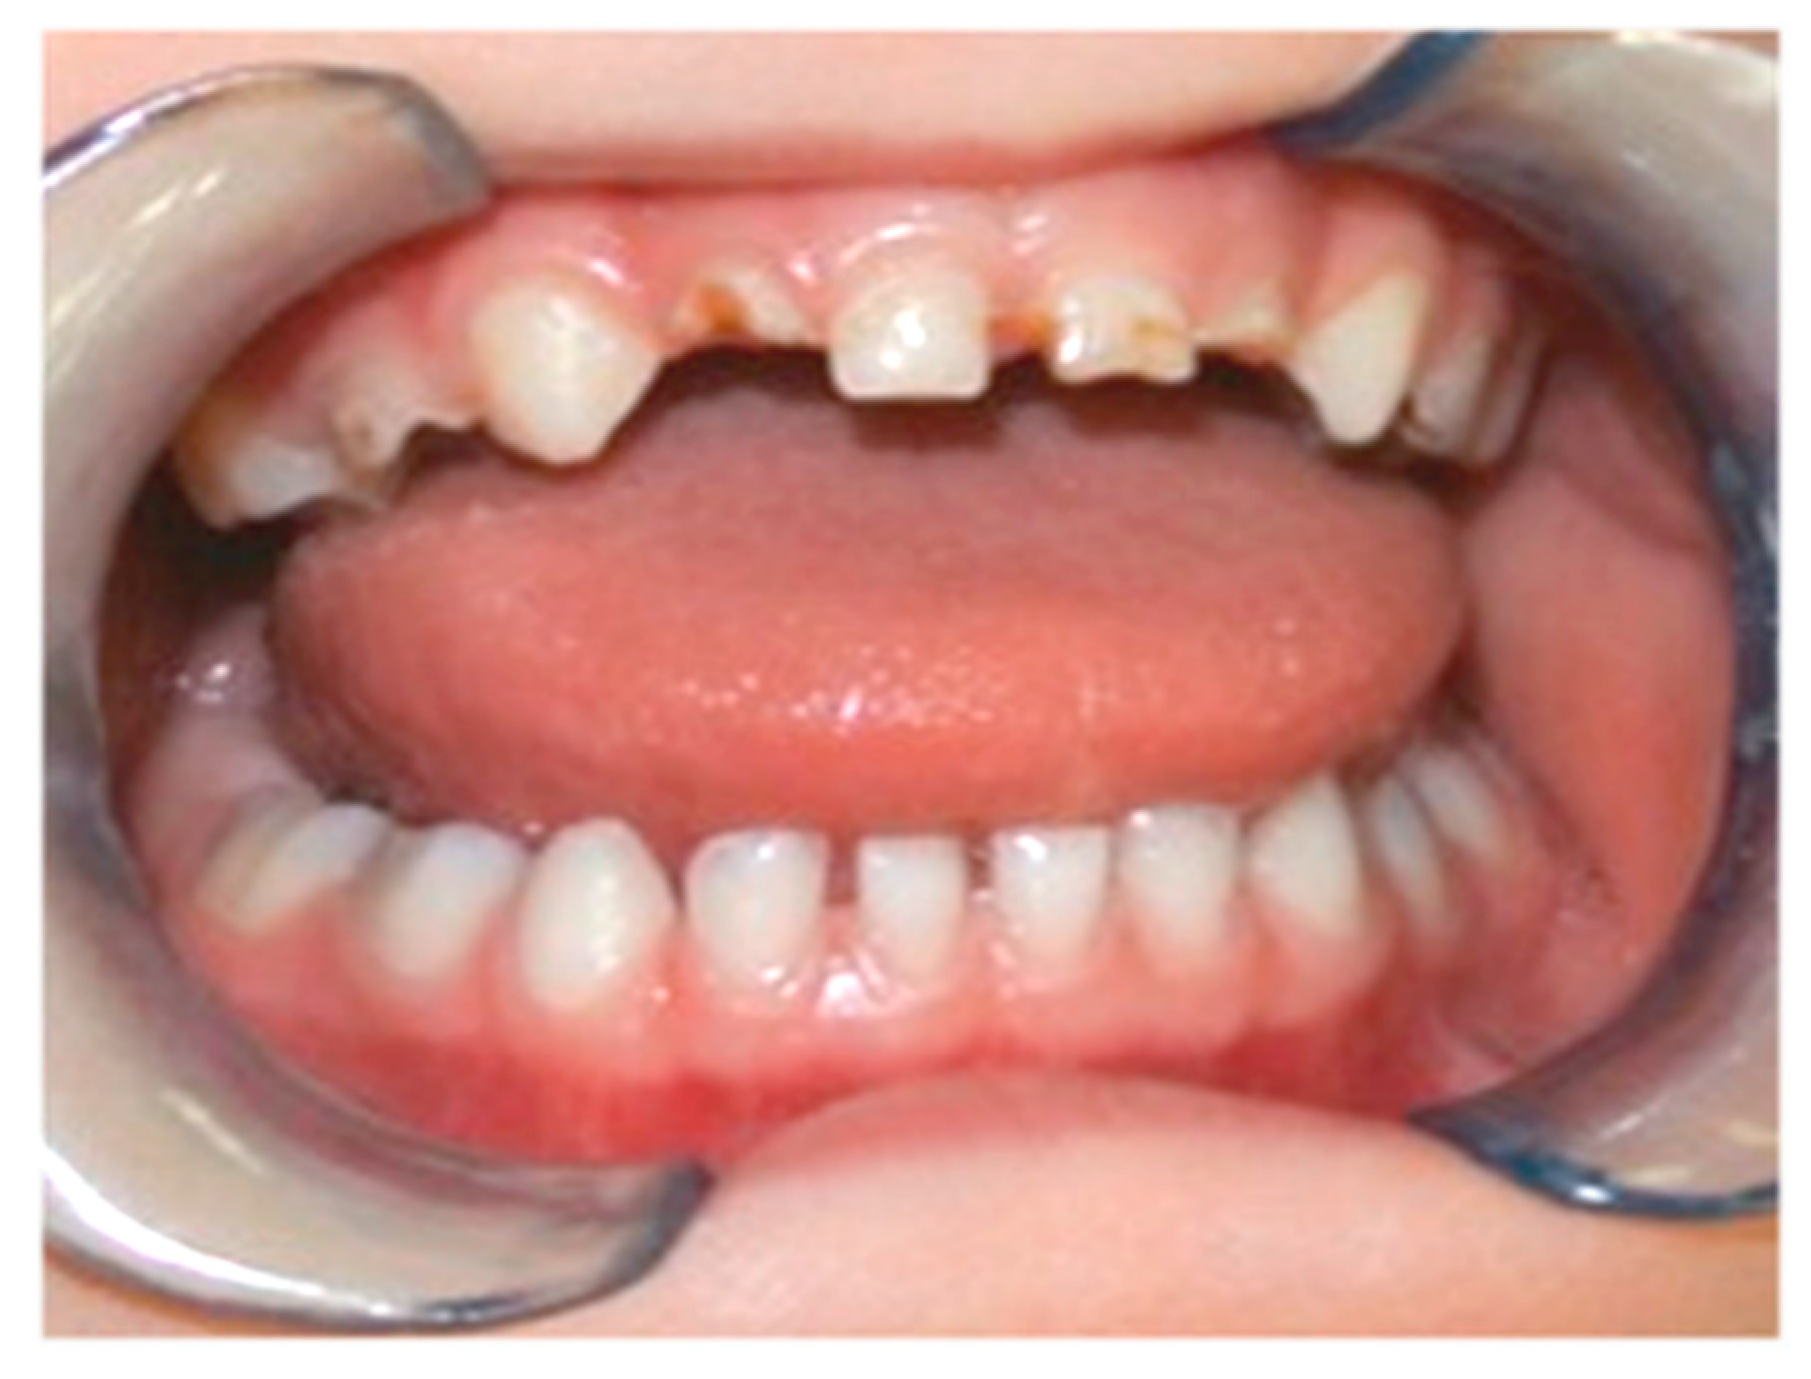

A total of 134 children (age: 2–17 years, mean ± SD: 5.5 ± 3.3 years, median: 4 years) who had previously exhibited ECC (Figure 1) and received dental treatment under general anaesthesia at the Department of Periodontology and Operative Dentistry of the Medical Center of the Johannes Gutenberg University Mainz, Germany, were initially invited by telephone call to return for regular dental visits.

Figure 1. Early childhood caries affecting the primary maxillary anterior teeth of a small child.